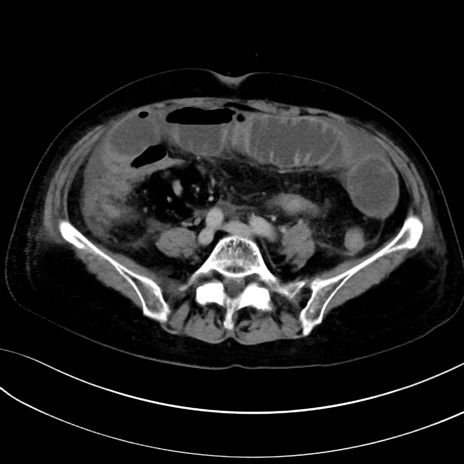

症例13 CT(横断像)1日半後